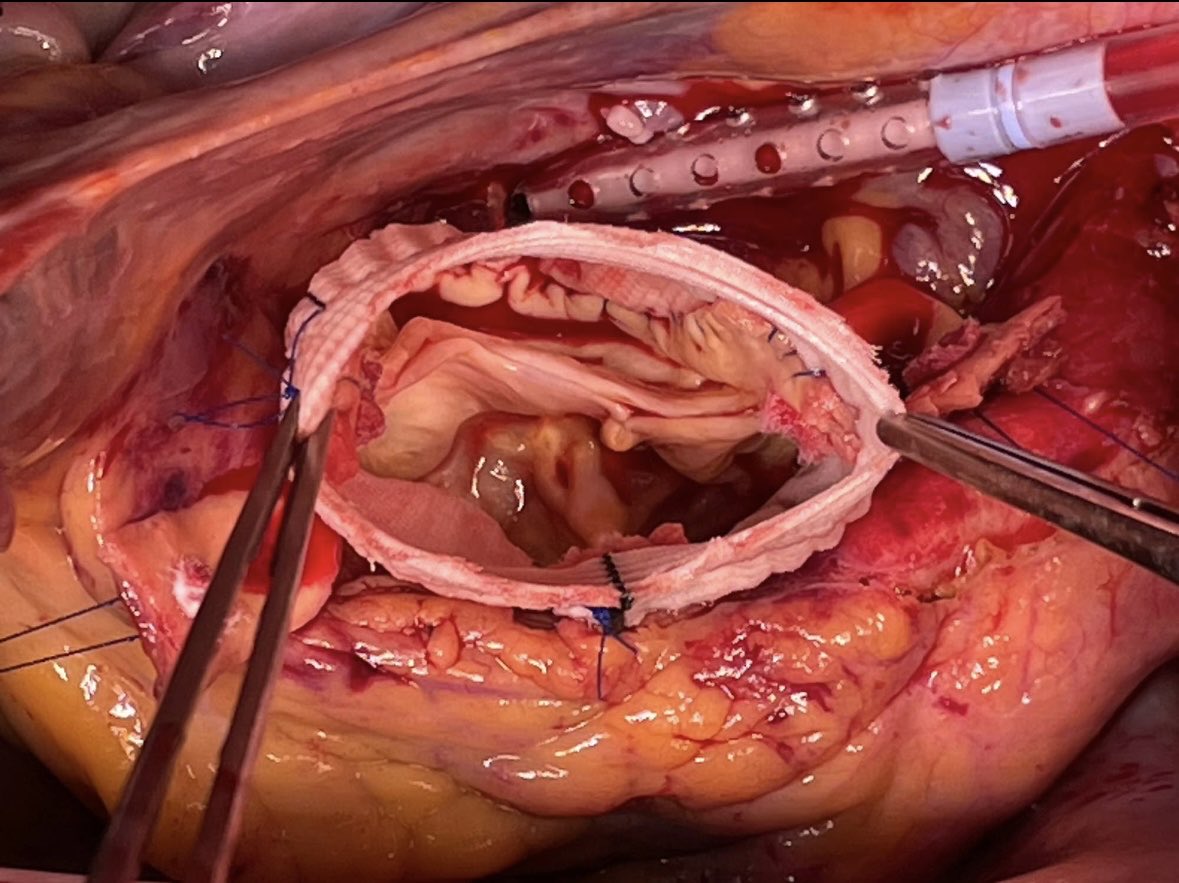

Our newest @JAHA_AHA review on the #RossProcedure is out today... a surgeon/cardiologist collaboration offering a modern look at patient selection, surgical technique, and long-term outcomes to guide practice.